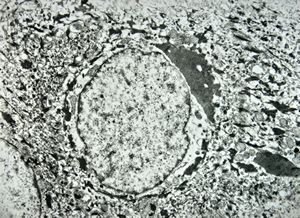

M, 48y. | multiplication of dermal perivascular basement membranes (unclassified myopathy)

F, 48y. | lupus erythematodes … multiplicated vascular basement membrane